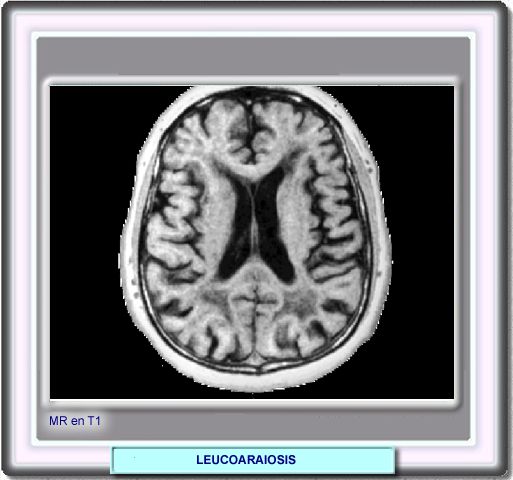

La RM en T1 no permite la detección de la leucoaraiosis, que por el contrario de observa en la RM en T2 y en la RM FLAIR